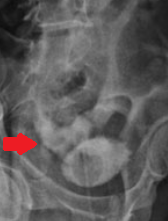

Κόκκινο βέλος — Εκτοπισμένος όρχις στην αριστερή βουβωνική χώρα. Κίτρινο βέλος — Δεξιός όρχις εντός οσχέου (Ευγενική παραχώρηση Dr. V. Penopoulos)